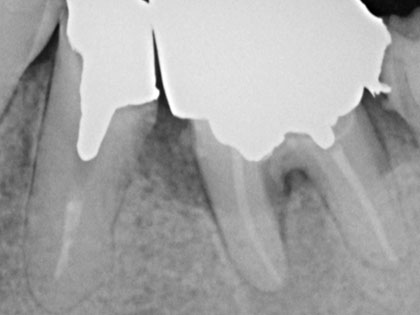

初診時のレントゲン写真がこちら

術前レントゲンの5番目、6番目の歯根間

6番目の分岐部(根本部分)の所が黒く抜けています

骨がとけています。